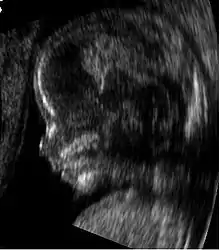

Sonogram of a fetus at 14 weeks (profile)

Head of a fetus, aged 29 weeks, in a "3D ultrasound"

The potential for ultrasonic imaging of objects, in which a 3 GHz sound wave could produce resolution comparable to an optical image, was recognized by Sergei Sokolov in 1939. Such frequencies were not possible at the time, and what technology did exist produced relatively low-contrast images with poor sensitivity.[34] Ultrasonic imaging uses frequencies of 2 megahertz and higher; the shorter wavelength allows resolution of small internal details in structures and tissues. The power density is generally less than 1 watt per square centimetre to avoid heating and cavitation effects in the object under examination.[35] Ultrasonic imaging applications include industrial nondestructive testing, quality control and medical uses.[34]

Medical ultrasound is an ultrasound-based diagnostic medical imaging technique used to visualize muscles, tendons, and many internal organs to capture their size, structure and any pathological lesions with real time tomographic images. Ultrasound has been used by radiologists and sonographers to image the human body for at least 50 years and has become a widely used diagnostic tool. The technology is relatively inexpensive and portable, especially when compared with other techniques, such as magnetic resonance imaging (MRI) and computed tomography (CT). Ultrasound is also used to visualize fetuses during routine and emergency prenatal care. Such diagnostic applications used during pregnancy are referred to as obstetric sonography. As currently applied in the medical field, properly performed ultrasound poses no known risks to the patient.[36] Sonography does not use ionizing radiation, and the power levels used for imaging are too low to cause adverse heating or pressure effects in tissue.[37][38] Although the long-term effects due to ultrasound exposure at diagnostic intensity are still unknown,[39] currently most doctors feel that the benefits to patients outweigh the risks.[40] The ALARA (As Low As Reasonably Achievable) principle has been advocated for an ultrasound examination  that is, keeping the scanning time and power settings as low as possible but consistent with diagnostic imaging  and that by that principle nonmedical uses, which by definition are not necessary, are actively discouraged.[41]